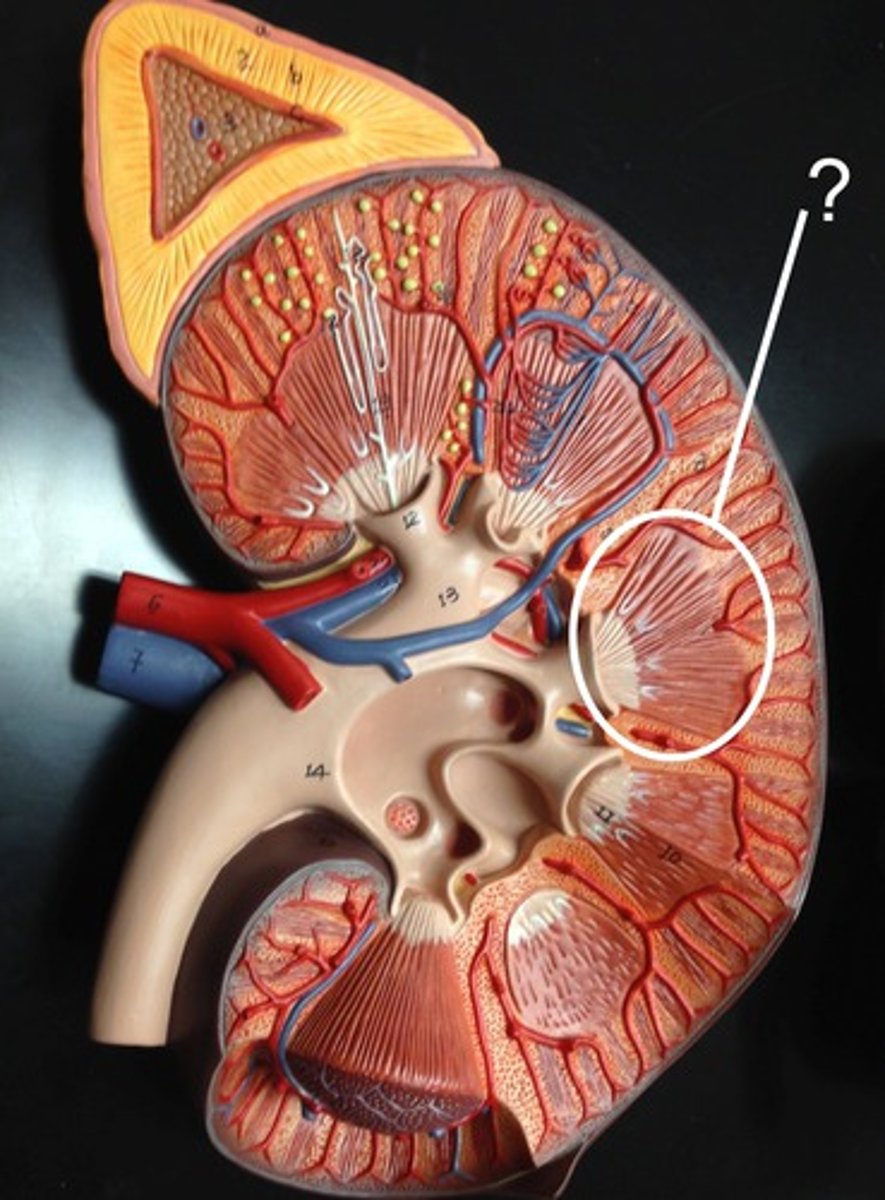

Cortical Nephron

N

Juxtamedullary Nephron

O

Renal pyramids

Peritubular capillaries

Vasa recta

Efferent arteriole

1

Afferent arteriole

2

Glomerulus

3

Bowman's capsule

4

Proximal convoluted tubule

5

6

Distal convoluted tubule

7

Loop of henle - thick portion

8

Loop of henle - thin portion

10

Collecting duct

11

Renal vein

F

Renal artery

G

Renal pelvis

H

Ureter

I

Minor calyx

L

Major calyx